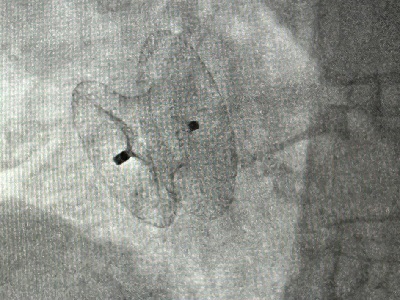

Z życia Szpitala – o zabiegu usunięcia tętniaka i guza mózgu podczas jednej operacji w Szpitalu Marciniaka we Wrocławiu